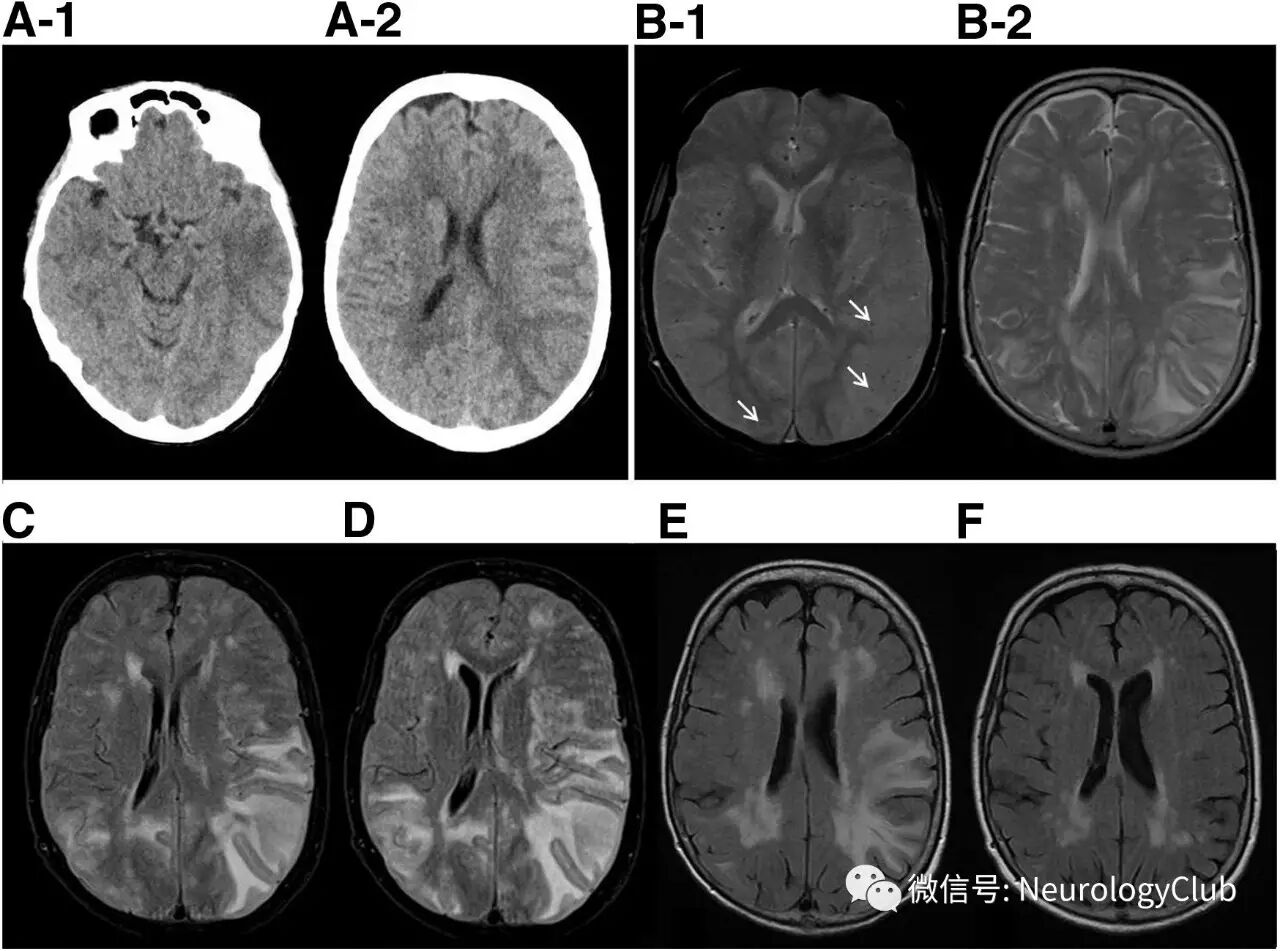

75岁女性,因突发失语入急诊。2天前也曾有过短暂性失语发作。既往有自身免疫性甲状腺炎、焦虑障碍、高血压和血脂异常。服用氟伐他汀、比索洛尔、左旋甲状腺素、阿普唑仑、溴替唑仑、多潘立酮、阿尔噻嗪和螺内酯。家族史无殊。无烟酒史。入院患者无发热,血压正常。神经系统查体除表达性失语外均正常。头颅CT提示左侧颞叶低密度病灶(图A)。考虑卒中收住内科病房。

随后几天,患者临床症状恶化,出现左侧大脑半球功能障碍,影像学病灶进展。连续的MRI(图B-D)可见白质病灶增多伴水肿,T2WI呈高信号,且T2*WI上提示多脑叶微出血(图B-1)。DWI上均未见弥散受限。患者入院12天后转至神经科。此时,患者无发热,但表现为意识水平下降,完全性失语和右侧轻偏瘫。

(图:A:入院CT可见左侧颞叶低密度;B-D:激素治疗前,入院第2天[B]、第4天[C]和第12天[D]的头颅MRI;T2*WI可见多发微出血[B-1,箭];T2WI[B-2]和FLAIR[C-D]可见融合性白质高信号病灶持续进展;激素治疗后,30天复查FLAIR上高信号病灶好转[E],9月后基本消失[F,残留的可能为年龄相关的白质病变])

考虑脑淀粉样血管病相关炎症,予静脉甲强龙1g/d治疗5天,改口服60mg泼尼松龙,逐渐缓慢减量,总疗程超过6月。激素治疗5天后,患者症状好转。15天后完全恢复,30天后复查MRI(图1E)病灶亦有所改善。

6月后,患者神经系统查体无局灶性功能缺失体征,9月后的MRI上病灶基本消失(图1F)。